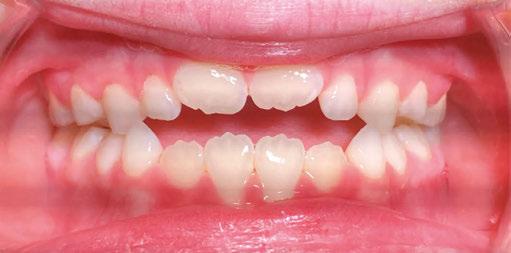

An 8-year-old Hispanic male presented to our private practice in Miami, Florida with the chief complaint of a missing front tooth (Figure 1). Upon review of his medical history, the mother revealed that her son had Autism Spectrum Disorder and confirmed that his condition was severe. This patient did not take

any medications, was nonverbal, avoided eye contact with any staff member including the treating pediatric dentist, did not sit in the dental chair, and was constantly tapping his ears. No dental radiographs were obtained due to his uncooperative behavior. For the dental exam, the mother agreed and consented with placing him in a passive restraining device. With a limited visualization of his oral cavity, a mixed dentition was noted. The maxillary right permanent central incisor was absent. No significant pathology was found in his oral soft tissues. Dental caries was found on both primary and permanent molars. A decision was made to complete dental treatment using general anesthesia as a behavior management technique at the local children’s hospital.

At the postoperative consultation with the mother, we told her the tooth’s complete root formation might prevent its eruption. Orthodontic extrusion of the incisor was ruled out due to his behavior. A conservative approach with observation only was elected as treatment modality. This patient returned for follow-up appointments at ages 10, 11, 12, and 13. During all these visits, the maxillary right permanent central incisor had not erupted. At age 14, due to recurrent dental caries, the patient was taken to the local children’s hospital for dental rehabilitation again. During this second hospitalization, we noticed that the right maxillary central incisor was partially erupted into the oral cavity (Figure 4).